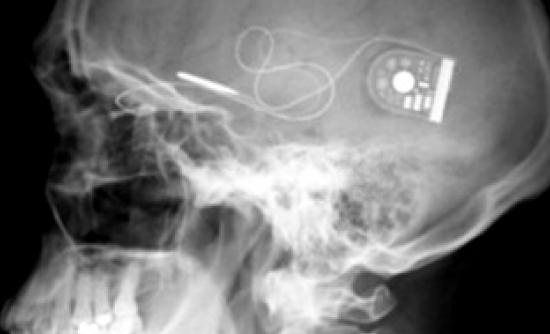

Το απίστευτα λεπτό και μικρό τσιπ που τοποθετήθηκε στο πίσω μέρος του ματιού των 2 ασθενών ανέλαβε να κάνει ακριβώς αυτή τη δουλειά. Τα 1500 φωτοευαίσθητα pixels, που έχει πάνω του, παίζουν πλέον τον ρόλο των ράβδων και των κώνων. Το φως που μπαίνει στο μάτι διεγείρει τα pixels, έτσι το μάτι το αντιλαμβάνεται, και στέλνει μήνυμα στο οπτικό νεύρο και από εκεί στον εγκέφαλο.